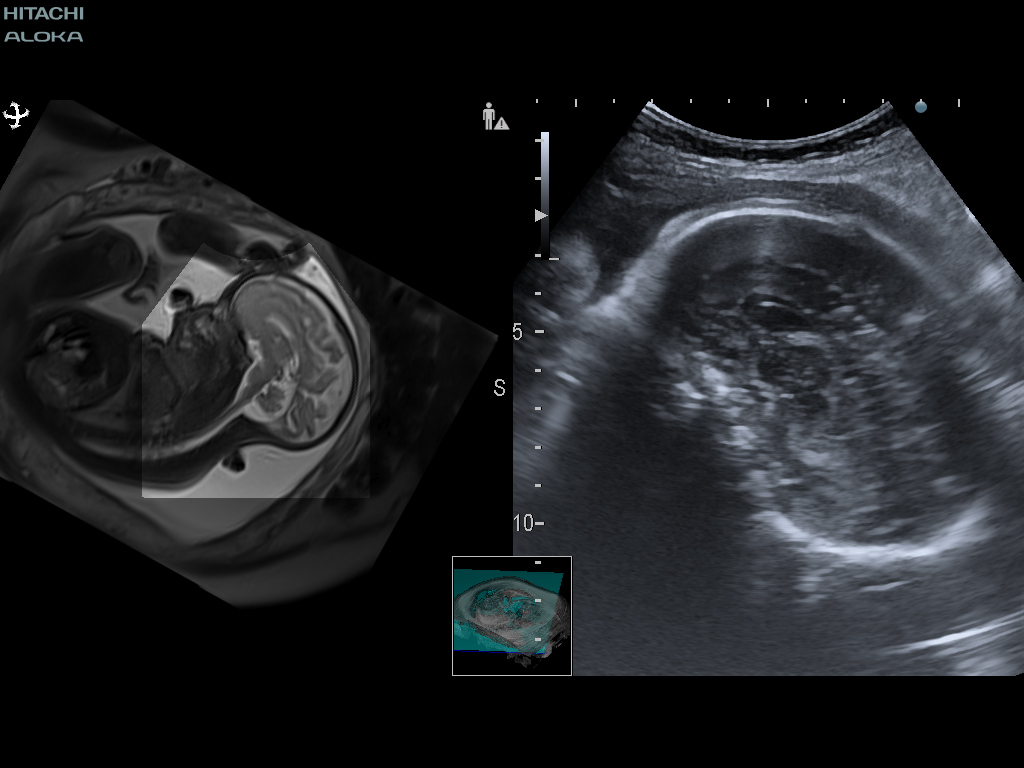

태아의 뇌 검사에서 실시간 가상 초음파 검사 (RVS)는 중뇌의 형성 (예 : pons and tegmentum), 특히 측두엽의 회전과 같은 특정 해부학 적 특징을 인식하는 데 도움이 될 수 있습니다.